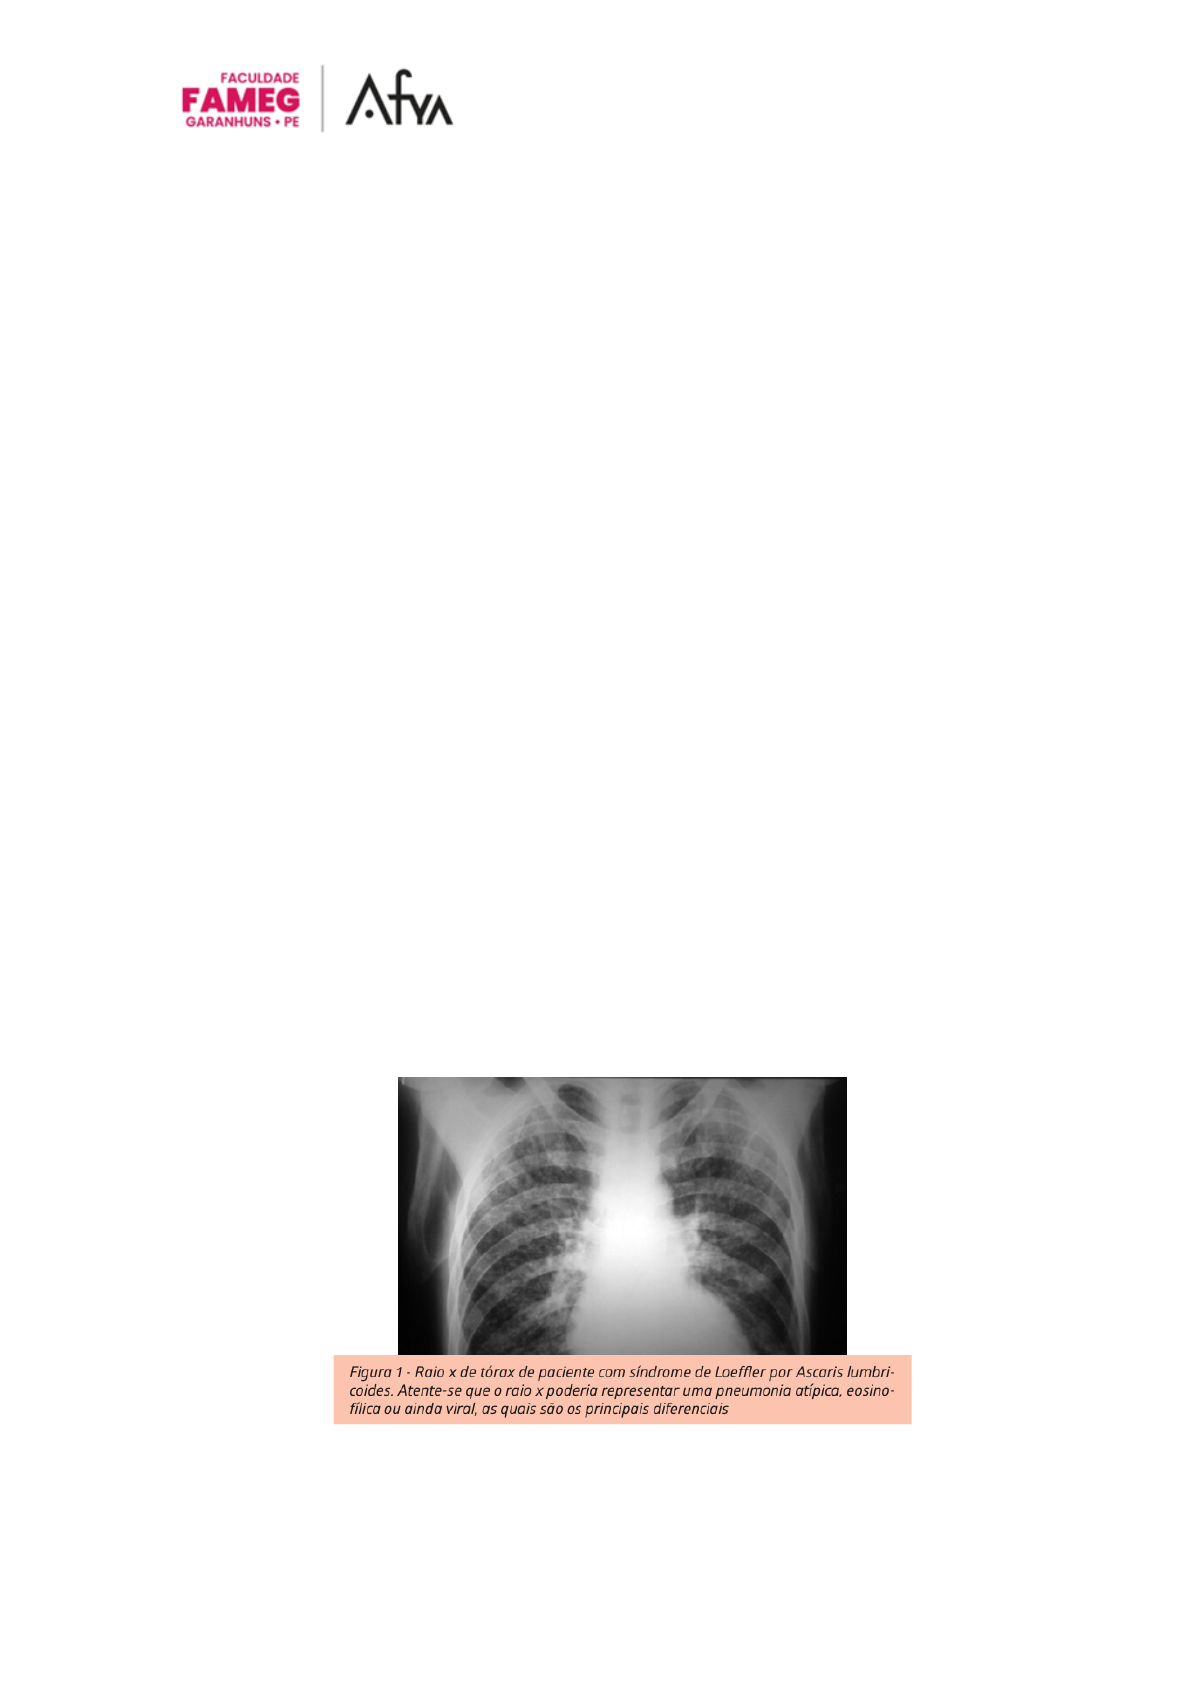

Nos exames de imagem os infiltrados são intersticiais, tendendo a ser migratórios e

múltiplos, eosinofilia é vista em lavado broncoalveolar e na biópsia transbronquica.